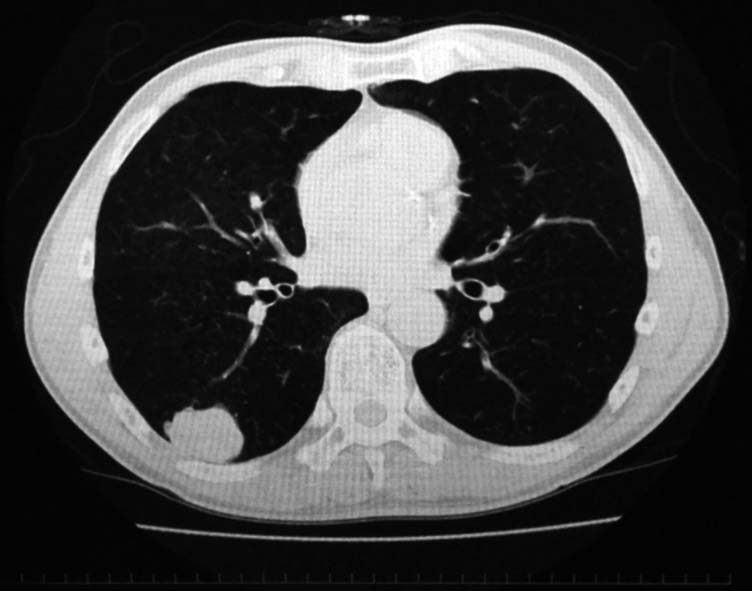

synovial sarcoma of the lung

IWTcase 59 y.o.

健診で2年ほど肺異常陰影を指摘されていたが自覚症状なく放置. 陰影が次第に増大, 精査のため受診する.

右肺下葉, S6bを主体に一部S9に広がる4.2x3.7x2.5cmの腫瘤. 辺縁凹凸不整, 胸膜に接し内部には不整形の小石灰化がある.肺癌疑い.気管支鏡TBBでは組織片が採取できなかった.

PETで原発巣にSUV max2.2の淡い集積. リンパ節には集積なし. 遠隔転移なし. 肺癌としてはPET集積が淡いが, cT2/1N0M0の肺癌であればstage1B~2Aとなり根治切除可能のためCTガイド下生検が施行された.